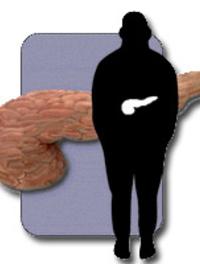

Des équipes américaines ont évalué la prévalence en 2005 du surpoids et de l’obésité de par le monde, chez les adultes âgés de plus [...]